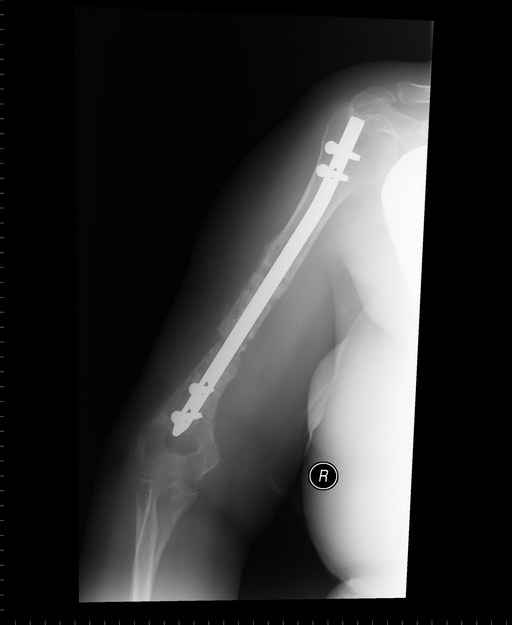

Больная 48 лет, медсестра-массажист, перелом плеча 7 лет назад, оперирована 4-кратно и безуспешно

Больная 48 лет, медсестра. Травма получена 7 лет назад, оперирована первично в Турции - остеосинтез пластиной - несращение - реостеосинтез стержнем там же через год (обычным, с выстоянеием его в полость плеча) - несращение - поступила к нам впервые в марте 2008 года - удаление стержня, реостеосинтез пластиной и костная пластика, в течение 2 лет лизис кости вокруг винтов, смещение фиксатора, в марте 2010 - удаление пластины, реостеосинтез интрамедуллярным стержнем с блокированием (рассверливание + костная пластика). В динамике - вновь лизис в области перелома, нестабильность дистальных блокирующих винтов.

Клинически фиксация пока действительно стабильна, но на рентгенограммах резорбция кости в области дистальных блокирующих винтов и миграция одного из них.